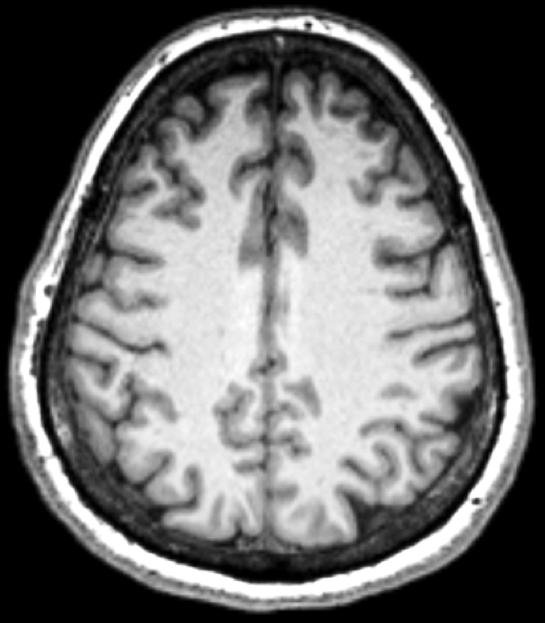

PhD: Multiple Sclerosis

Disease Progression

Relapse Remitting vs Progressive

Treatment = f(Disease progression)

But we don't know Dp early on

A clue to Dp ?

Big Data Collection

500 patients, 12 years

= 6,000 MRI scans